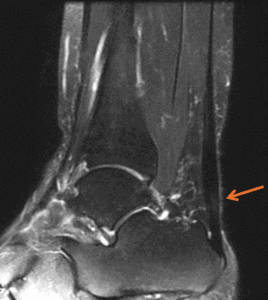

・MRI検査:腱の変性程度や周囲の滑液包炎の有無を確認

※アキレス腱実質に肥厚と交信劫初軒あり。